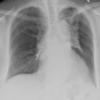

Pulmonary Fibrosis

IPF